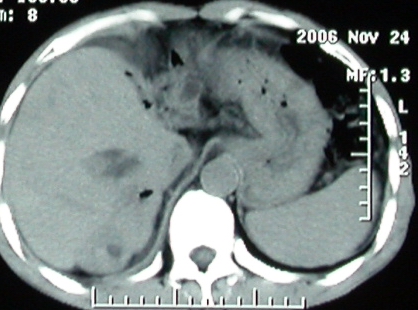

标题: 上腹隐痛、饱胀、消瘦2-月。

增强ct所见【动脉增强期】

手术结果:

肝脏尾状叶肝癌(沿肝十二指肠韧带向下韧带内生长,门腔间隙外压增大),大结节性肝硬化,胆囊积脓,胆道感染。术中见肝外胆道2cm直径,肿瘤向前压迫胆管至扁平状态。